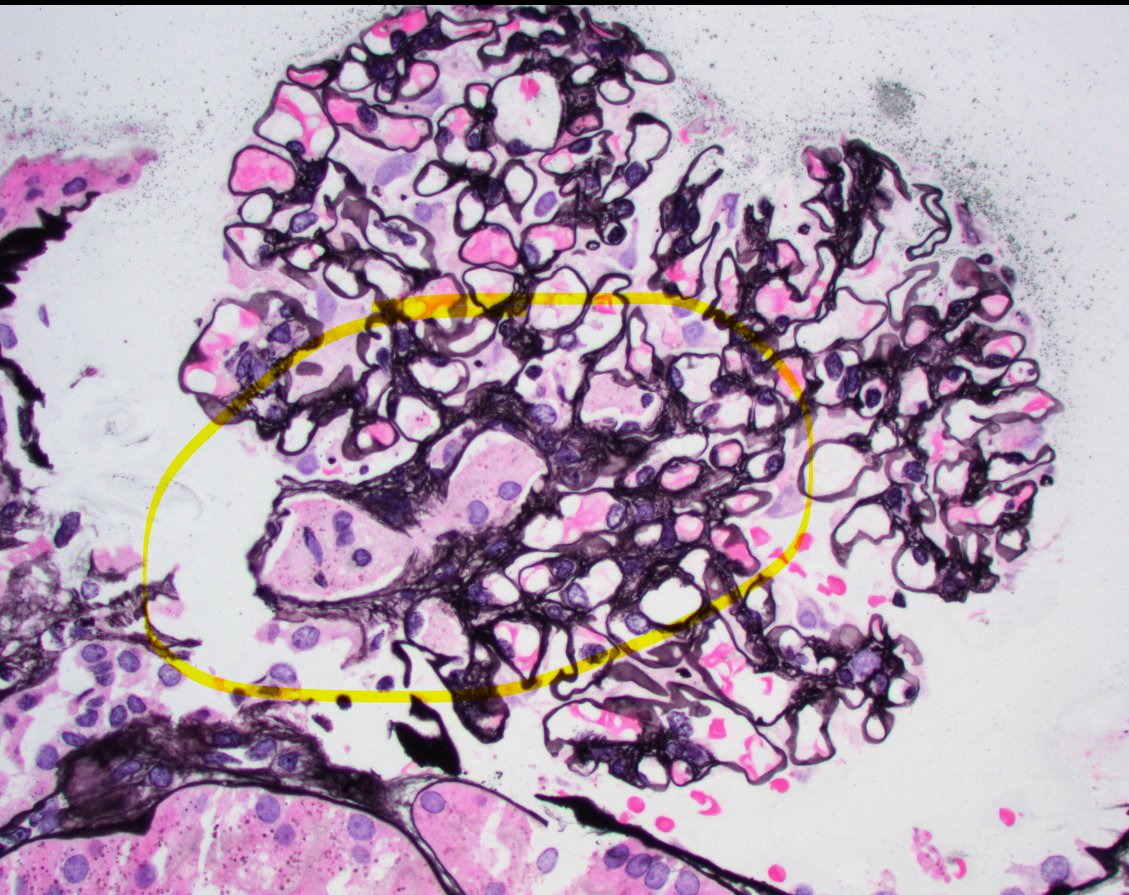

Arteriole with features of a old recanalized thombus in a transplant kidney biopsy. Multiple slit like vascular spaces within the fibrotic lumen. Not a lesion I see often. Pt had clinically diagnosed TMA a few months prior. #renalpath #pathtwitter #nephrology